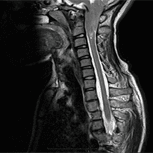

La scoperta eziologica del Dott. Royo considera che un legamento, il Filum terminale, con una tensione anomala a livello congenito, sia causa di una trazione eccessiva su tutto il sistema nervoso centrale (SNC); tutto ciò costituisce la Malattia del Filum (MF). Una delle conseguenze, tra varie, è la discesa di tutto il sistema nervoso, compresa la sua porzione inferiore del cervelletto- le tonsille cerebellari- attraverso il foro occipitale, ectopia propria della sindrome.

A differenza del MA e del MAO, nei quali il Filum Terminale può ancorare il midollo a diversi livelli e in modo visibile nelle risonanze magnetiche, e che sono completamente distinte all’Arnold Chiari I, nel quale non c’è nessuna evidenza di alcun ancoraggio midollare, invece il paradigma implicito nella definizione della Malattia del Filum contribuisce alla comprensione della discesa delle tonsille come due entità patologiche strettamente connesse tra loro, in quanto la prima è la causa e la seconda la conseguenza.